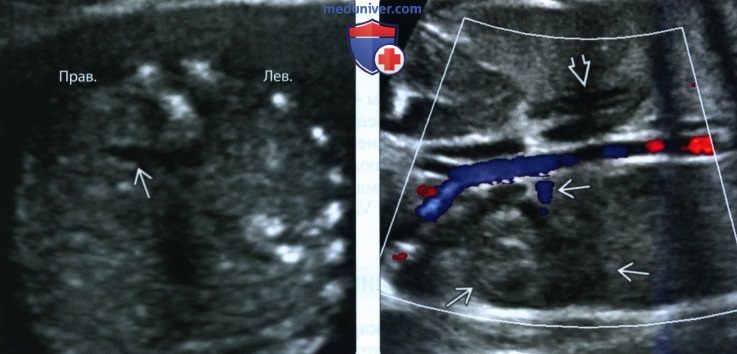

Медицинские изображения и объяснения агенезии почки

Раздел: Снимки-откровения